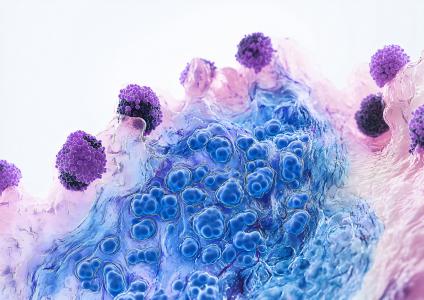

POLLUTION et DÉMENCE : Les particules fines font des corps de Lewy

Ce lien moléculaire entre les polluants atmosphériques et un risque accru de démence à corps de Lewy, identifié par une équipe de neuroscientifiques de la Columbia University's Mailman School of Public Health, met à nouveau en exergue les effets délétères des particules fines (PM2,5). Ces travaux, publiés dans la revue Science, s'ajoutent à un nombre croissant de preuves indiquant comment ces facteurs environnementaux déclenchent des modifications protéiques nocives dans le cerveau, responsables de neurodégénérescence.